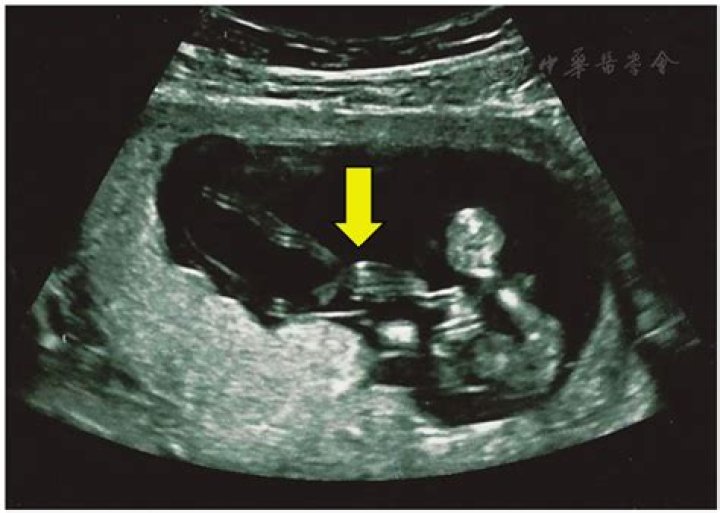

Two umbilical cords were seen coming from the common placenta. The cord of the normal twin was long and edematous with a pair of umbilical arteries and one umbilical vein. The umbilical cord of the acardiac twin was short with a single umbilical artery and a single vein.